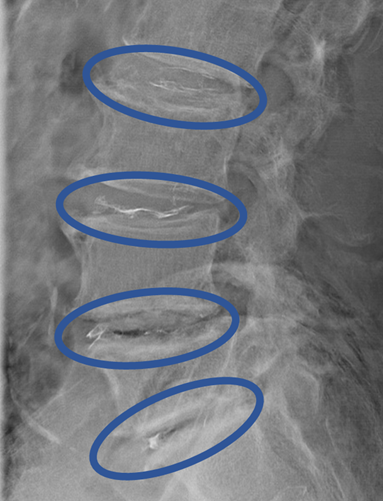

画像及び所見について

L1/2: 変性

L2/3: 変性、膨隆

L3/4: 変性、膨隆、左椎間孔狭窄

L4/5: 変性、膨隆、両側椎間孔狭窄、LSS

L5/S: 変性、膨隆

以上の事が画像上認められます。

L2/3、3/4、4/5、5/Sに

脊柱管狭窄症、椎間板変性、椎間孔狭窄症を認め、主症状の原因の可能性が高い。

DiscoGelを入れた後の画像になります。